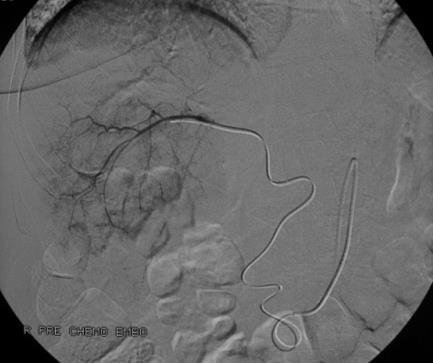

1. 需要超选择血管导管置入?Catheter Placement Selective? 这是必须的,因为可以 2. 较好地微粒控制(Better control) 3. 最少的返流(Minimize reflux)以及 4. 微粒在瘤内的可视性好(Better visualization of beads)。 5. 应用C-arm CT可以在栓塞前,验证栓塞的正确性。肿瘤可视(visualize the tumor)

技术成功的证明,意味着可以获得预期中的肿瘤反应,也意味着药物灌注到肿瘤段(Perfusion tumor segmentation) 6. 与造影剂混合比例 4:1 7. 注射缓慢,每分钟注射1ml;避免导管嵌顿在血管中保留血流动力学;间断晃动注射器,使微粒均匀;稀释很重要

8. 灌注终点是计划中的剂量完全灌注到肿瘤内 9. 发生反流前停滞或肝动脉2~3级分支停滞,返流前停止注射

10. 停止注射后,10分钟再造影观察,是否需要再注射 11. 不需要进一步不含药物的空载微粒注射 12. 治疗终点:一次治疗完全去血管化,还是多次治疗实现去血管化。